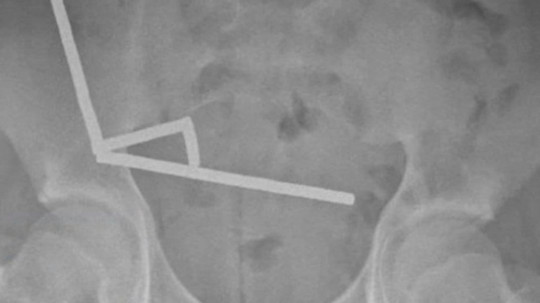

Yeni Zelanda'da yaşanan tıbbi vakada, 13 yaşındaki bir çocuğun yuttuğu yaklaşık 100 mini neodyum mıknatıs, bağırsak dokusunda ciddi hasara yol açtı. New Zealand Medical Journal dergisinde yayımlanan vaka raporuna göre, günler süren karın ağrısı şikayetiyle hastaneye getirilen çocuğun röntgen görüntülerinde, karnının sağ alt bölgesinde birbirine yapışmış metal yığınları tespit edildi.